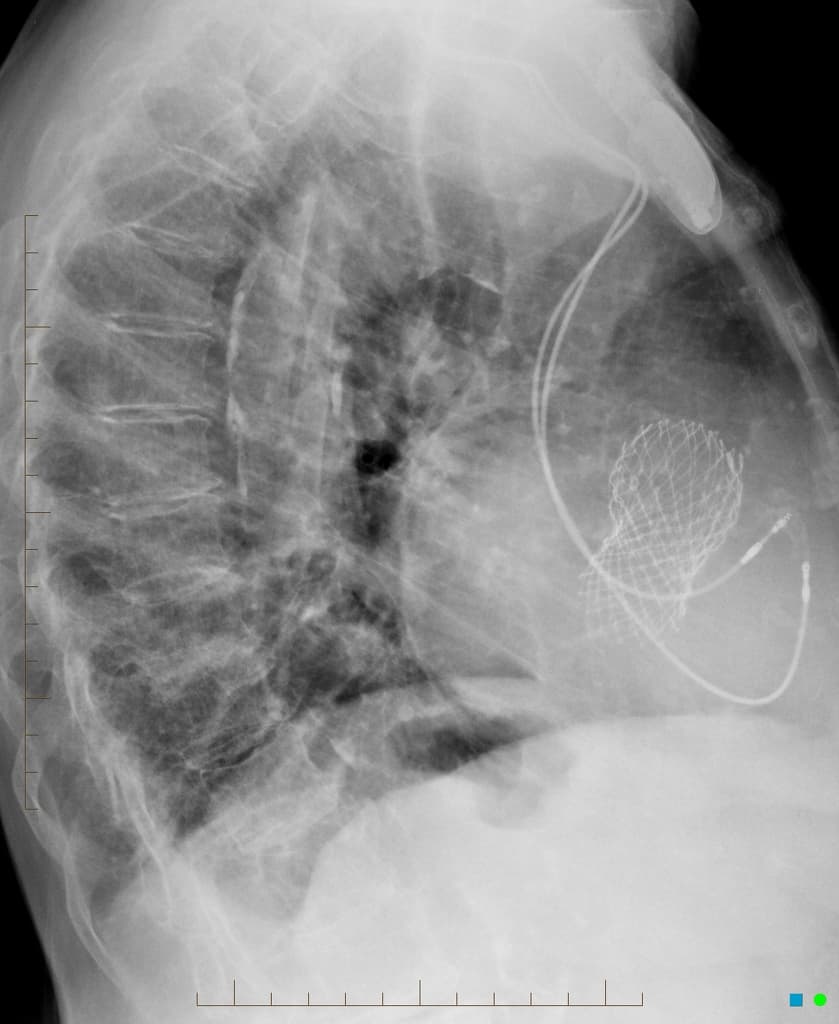

Lateral

- Quan sát rõ nhất trên phim nghiêng là hình ảnh thay van động mạch chủ qua ống thông (transcatheter aortic valve replacement - TAVR), còn được gọi là cấy van động mạch chủ qua ống thông (transcatheter aortic valve implantation - TAVI).

- Máy tạo nhịp (pacing device) hai dây dẫn bên trái tại chỗ (in situ).

- "Khớp giả TAVR thường được nhìn thấy trong gốc động mạch chủ và thường được quan sát tốt nhất trên phim X-quang ngực nghiêng."

Thay van động mạch chủ qua ống thông (TAVR), còn được gọi là cấy van động mạch chủ qua ống thông (TAVI), là một phương pháp thay thế cho phẫu thuật thay van động mạch chủ (SAVR) cho những bệnh nhân bị hẹp van động mạch chủ nặng có triệu chứng, đặc biệt là những người có nguy cơ phẫu thuật cao. Thủ thuật này bao gồm việc triển khai một van sinh học thông qua ống thông, thường là qua đường động mạch đùi. Trên hình ảnh, van xuất hiện dưới dạng một khung giống stent cản quang nằm ở mức vòng van động mạch chủ. Các bác sĩ chẩn đoán hình ảnh nên biết về hình dạng điển hình này để tránh nhầm lẫn với các van phẫu thuật và để theo dõi các biến chứng như di lệch van hoặc việc đặt các thiết bị hỗ trợ tim liên quan.